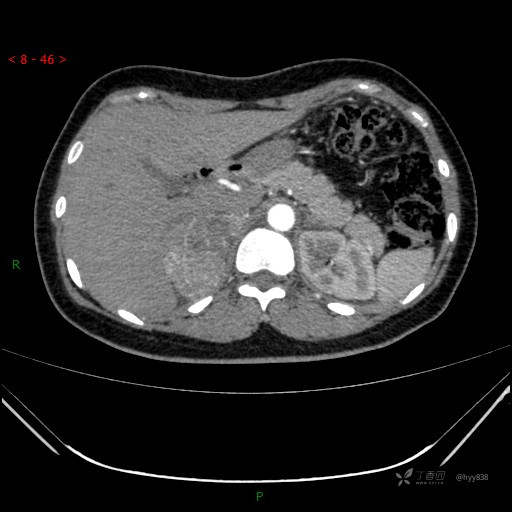

肾上腺CT平扫